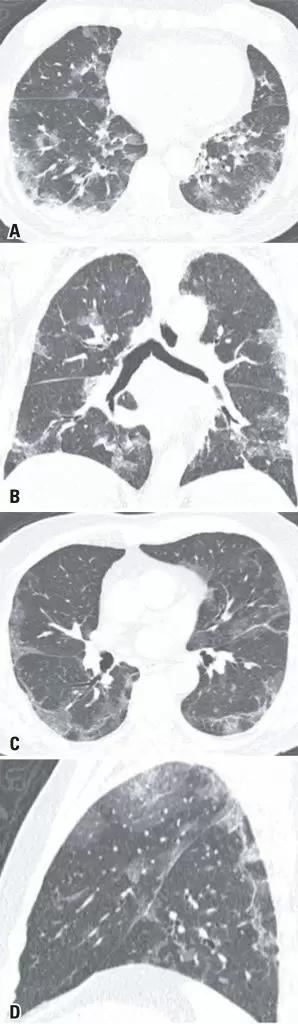

The COVID-19 became a pandemic in early 2020. It was found, at first, that the main manifestations of this new virus occur through respiratory and constitutional symptoms. Therefore, chest tomography was elected as the best imaging test to assess the extent of pulmonary involvement and as a good prognostic predictor for the disease. However, as new studies were produced, the gastrointestinal involvement of COVID-19 becomes more evident, with reports from patients who manifested mainly or only gastrointestinal symptoms in the course of the disease. Thus, in some cases, the initial investigation is carried out at the emergency department with an abdominal computed tomography. We report a case series of ten patients who came to the emergency department of our institution with a chief gastrointestinal complaint, and were initially submitted to an abdominal computed tomography as the first investigation. Although most of the patients did not have significant changes in the abdominal images, most reported patients had pulmonary findings visualized at the lung bases, which were later designated as typical COVID-19 pulmonary findings on chest computed tomography. Only one patient had atypical COVID-19 lung changes on chest computed tomography. All patients had a positive real-time polymerase chain reaction for COVID-19. It is imperative to alert radiologists, especially abdominal radiologists, with the possibility of COVID-19 isolated gastrointestinal symptoms. Besides, it must become a habit to radiologists to assess the pulmonary basis on abdominal scans, a site commonly affected by the new coronavirus.